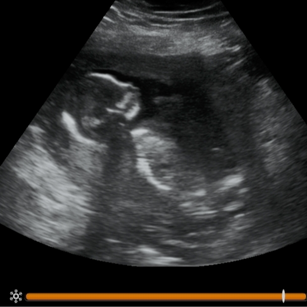

16 Weeks Pregnant

Size: ~4.5 inches (11.5 cm), the size of an Avocado!

16 Weeks 1 Day Pregnant